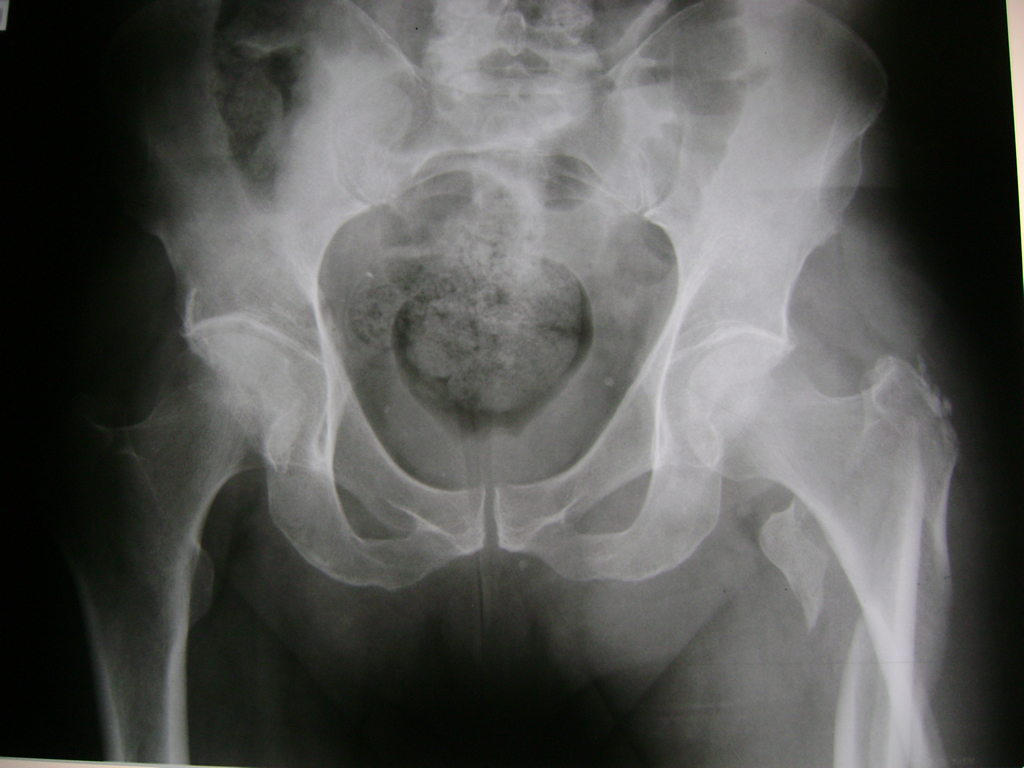

La cirugía de fractura de cadera se realiza para reparar una ruptura en la parte superior del hueso del muslo. Este hueso se denomina fémur.

Es parte de la articulación coxofemoral. Si una fractura de cadera no recibe tratamiento, es posible que deba permanecer en una silla o en la cama.

Esto puede llevar a otros problemas de salud potencialmente mortales, sobre todo si usted es una persona mayor.

A menudo se recomienda la cirugía para reparar la fractura debido a dichos riesgos.